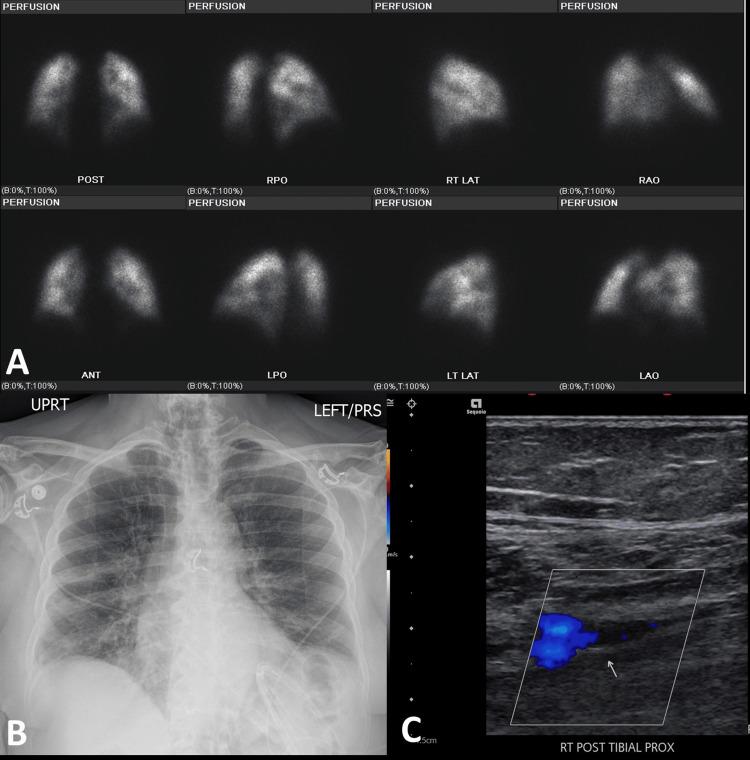

Introduction The COVID-19 pandemic has profoundly impacted medical practices, including nuclear medicine. To minimize aerosol transmission risks, lung perfusion scintigraphy was preferred over traditional ventilation-perfusion (V/Q) scintigraphy during the pandemic. This study compares lung perfusion scans performed during COVID-19 with V/Q scans from the pre-COVID era. After reviewing this study, the reader will learn about V/Q scintigraphy and lung perfusion. Methods This retrospective observational study, conducted from December 2018 to July 2021, involved 868 patients - 511 in the pre-COVID era and 357 in the post-COVID era - at a single tertiary care center. The pretest probability of pulmonary embolism (PE) was determined using Wells' criteria, and data including demographics, clinical findings, and diagnostic test results (V/Q or lung perfusion scintigraphy) were collected. Results A 30% decline in lung scans was observed during the pandemic. In the pre-COVID era, 68.3% of scans had low, 27.8% had intermediate, and 3.9% had high probability for PE. During the pandemic, perfusion-only scans showed 57.3% low, 32.9% indeterminate, and 9.8% high probability for PE. Among COVID-19-positive patients, 48.9% had intermediate, and 11.1% had high probability scans. The rise in indeterminate and high-probability scans during the pandemic is attributed to COVID-19-related lung changes and hypercoagulability. Conclusion The perfusion component of lung scans is typically sufficient for evaluating acute PE. Omitting the ventilation part of the V/Q scan had minimal impact, with only a 5.1% increase in indeterminate/non-diagnostic scans using perfusion-only modified Prospective Investigation of Pulmonary Embolism Diagnosis II (PIOPED II) criteria during the post-COVID-19 era, likely due to underlying lung parenchymal involvement in COVID-19 patients. Additionally, there was a 5.9% rise in high-probability scans, attributed to the hypercoagulability and vascular complications associated with COVID-19.

摘要

引言

新冠疫情对包括核医学在内的医疗实践产生了深远影响。为了将气溶胶传播风险降至最低,在疫情期间,肺灌注闪烁扫描比传统的通气-灌注(V/Q)闪烁扫描更受青睐。本研究比较了新冠疫情期间进行的肺灌注扫描与新冠疫情前时代的V/Q扫描。阅读本研究后,读者将了解V/Q闪烁扫描和肺灌注。

方法

这项回顾性观察研究于2018年12月至2021年7月在一家三级医疗中心进行,涉及868例患者,其中新冠疫情前时代511例,新冠疫情后时代357例。使用Wells标准确定肺栓塞(PE)的预测试概率,并收集包括人口统计学、临床发现和诊断测试结果(V/Q或肺灌注闪烁扫描)的数据。

结果

疫情期间观察到肺扫描下降了30%。在新冠疫情前时代,68.3%的扫描PE概率低,27.8%为中等,3.9%为高概率。在疫情期间,仅灌注扫描显示57.3%概率低,32.9%不确定,9.8%概率高。在新冠阳性患者中,48.9%为中等概率,11.1%为高概率扫描。疫情期间不确定和高概率扫描的增加归因于与新冠相关的肺部变化和高凝状态。

结论

肺扫描的灌注部分通常足以评估急性PE。省略V/Q扫描的通气部分影响最小,在新冠疫情后时代,仅使用灌注的改良肺栓塞诊断前瞻性调查II(PIOPED II)标准,不确定/非诊断性扫描仅增加了5.1%,这可能是由于新冠患者潜在的肺实质受累。此外,高概率扫描增加了5.9%,这归因于与新冠相关的高凝状态和血管并发症。